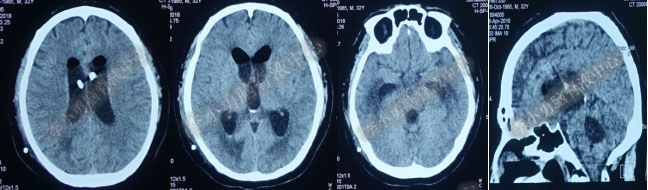

图-9:2017年10月15日头部CT

第4次出院后11天即2018年4月15日(分流术后284天,第2次的软性内镜术后179天),因引流管堵塞第5次住入该院,引流管内白色絮状物增多,引流管被堵塞。入院当天复查头部CT(图-10)显示脑室系统仍扩张。

图-10:2018年4月15日头部CT

第5次入院第2天即2018年4月17日,脑室腹壁外引流管堵塞,意识恶化,复查头部CT(图-11)示全脑室系统又较前扩大。当天急诊行左侧脑室穿刺外引流术。脑脊液化验外观黄色浑浊,并且送培养,结果是无菌生长。

图-11:2018年4月17日头部CT脑室扩张又加重